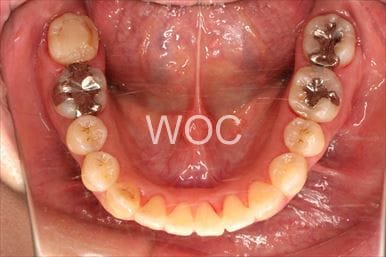

治療中1

-